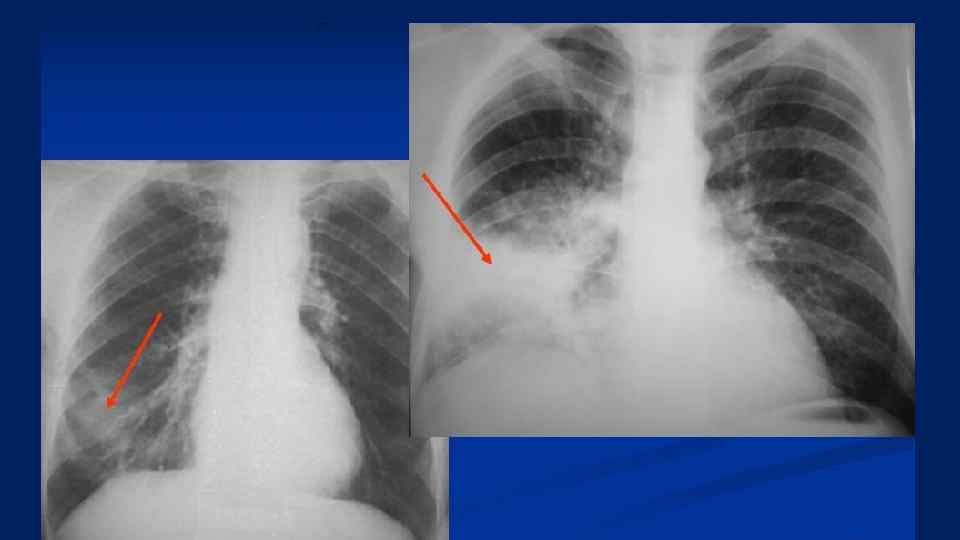

А Б А. Бронхопневмония. Стрелками указаны очаги уплотнения легочной ткани (инфильтраты). Б. Долевая пневмония – стадия серого опеченения.